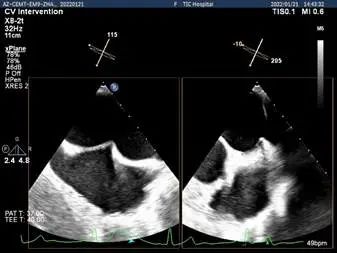

确定房间隔穿刺点:中部靠后

穿刺点高度测量:4.39cm

3D视图菲薄的卵圆窝,穿刺点位于房间隔中部略靠前,3点略偏2点位

2D视图下判断大鞘位置及长度

2D视图下trajactiory

x-plane验证前后叶抓捕后bond明显